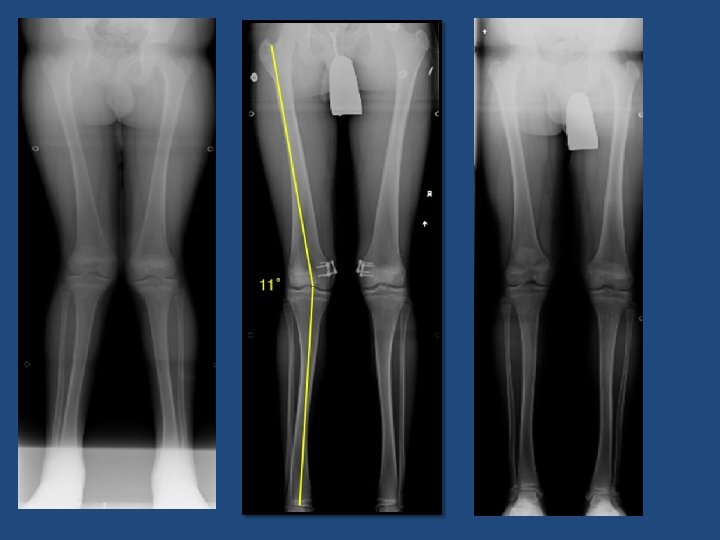

Radiological Parameters Lateral Distal Femoral Angle (LDFA) Medial Proximal Tibia Angle (MPTA) Mechanical Axis (MA) Comprehesive treatment of late –onset tibia vara Gordon JBJS 2005

Genum Valgum 10 -20° of valgus in a patient <10 years of age if line drawn from center of femoral head to center of ankle falls in lateral quadrant of tibial plateau in patient > 10 yrs of age Physeal stapling for idiopathic genu valgum Stevens JPO 1999

Genum Varus if line drawn from center of femoral head to center of ankle falls in medial quadrant of tibial plateau in patient > 10 yrs of age

Castañeda et al JPO 2008 48 pts Correction rate: Proximal tibia : 5. 5 degrees per year Distal Femur : 6. 7 degrees per year Hemiepiphysiodesis for correction of angular deformity about the knee Castañeda JPO 2008